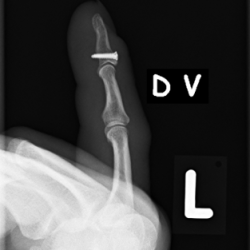

Röntgenbilder